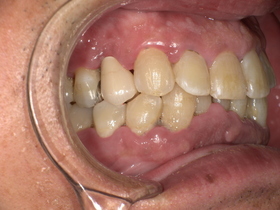

治療前の状態|詰め物の劣化と二次虫歯

診察の結果、以下の問題が確認されました。

■ 二次虫歯(再発虫歯)

詰め物と歯の隙間から細菌が侵入し、

👉 内部で虫歯が進行している状態

■ 適合不良(段差・隙間)

- 汚れが溜まりやすい

- 歯周病リスク増加

■ 噛み合わせの乱れ

欠けた状態を放置していたため、

👉 他の歯に負担がかかっていました

症例結果|Before / After

Before

- 詰め物が脱離

- 清潔感に欠ける状態